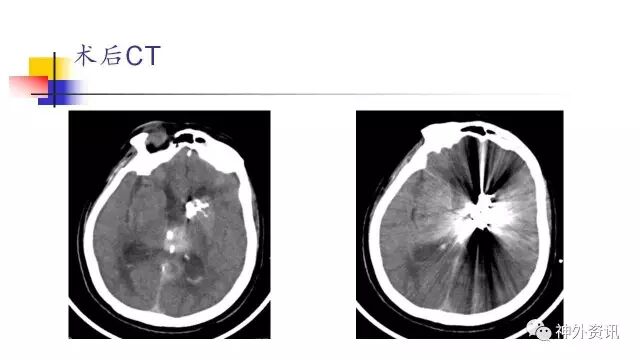

手术过程